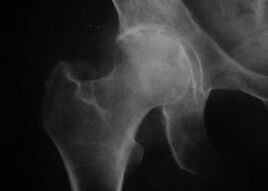

Aparência de uma articulação com artrose

Coxatrose, artrose da articulação do quadril

Nessa doença, observa-se um quadro clínico clássico de artrose.

O primeiro sintoma da coxartrose é o desconforto na articulação do quadril após atividade física.

Com a coxartrose progressiva, a dor aumenta, aparecem rigidez e dificuldade de mobilidade.

Pacientes com coxartrose grave poupam o membro afetado, evitando pisar nele e, enquanto parados, escolhem posições em que a dor seja menos sentida.